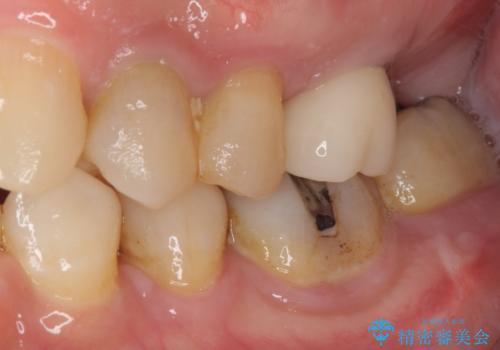

根管治療を行ったままの奥歯 オールセラミッククラウンによる補綴治療

- 以前根管治療を行い、クラウンにする必要があると言われたものの、そのままに放置してしまったとのことで来院された患者様です。

根管治療を行った歯には特に症状がないため、速やかにオールセラミッククラウンにて補綴治療を行うこととしました。

補綴治療前は食後はいつもものが挟まっていたそうですが、補綴治療後はものが挟まる悩みから解放されたとのことでした。